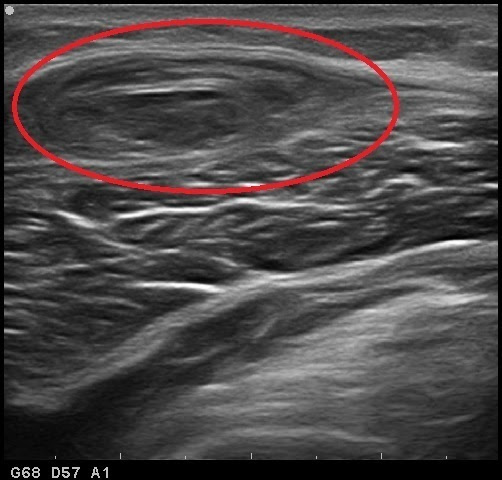

①【大腿部打撲とは?】

④【診断方法】